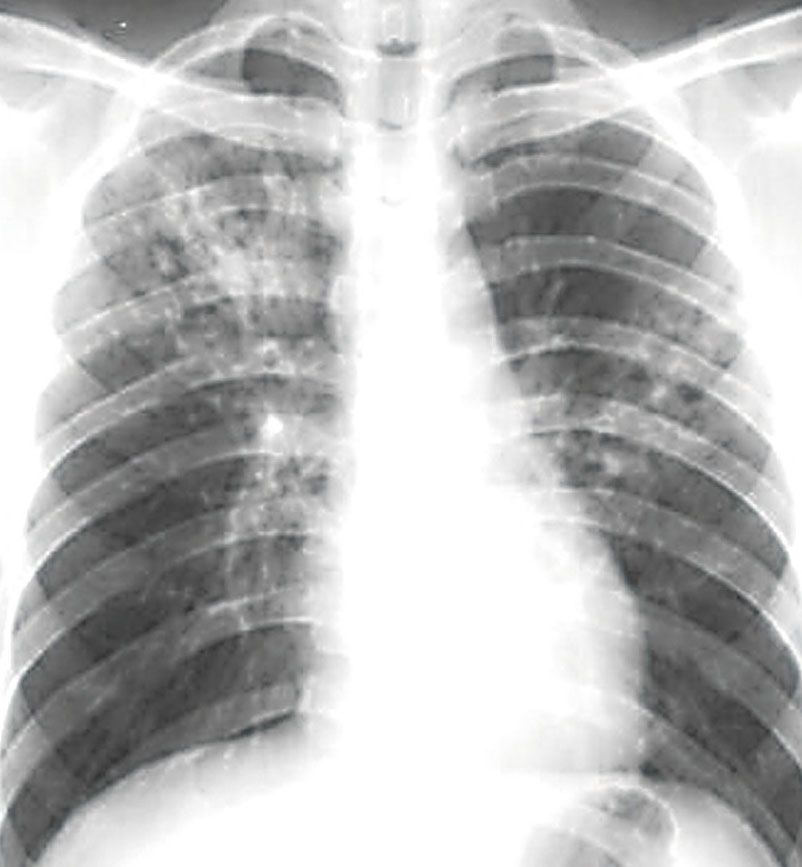

2.如何发现及诊断结核病

可以通过X线检查及显微镜下痰涂片检查。病人留三个痰标本,分别为夜间痰、晨间痰、即刻痰。留痰时病人应做深呼吸后用力咳嗽以咳出气管深部的痰。痰菌检查如发现了结核菌即可确定为传染性肺结核病人。这是诊断肺结核的主要依据。